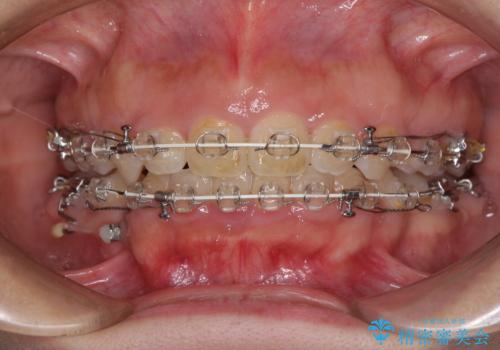

- 矯正装置

- 審美装置

- 4年5ヶ月

- 10-30回

上下左右の小臼歯4本を抜歯し、ワイヤー装置にて口元を引っ込めるよう矯正治療を行うこととしました。